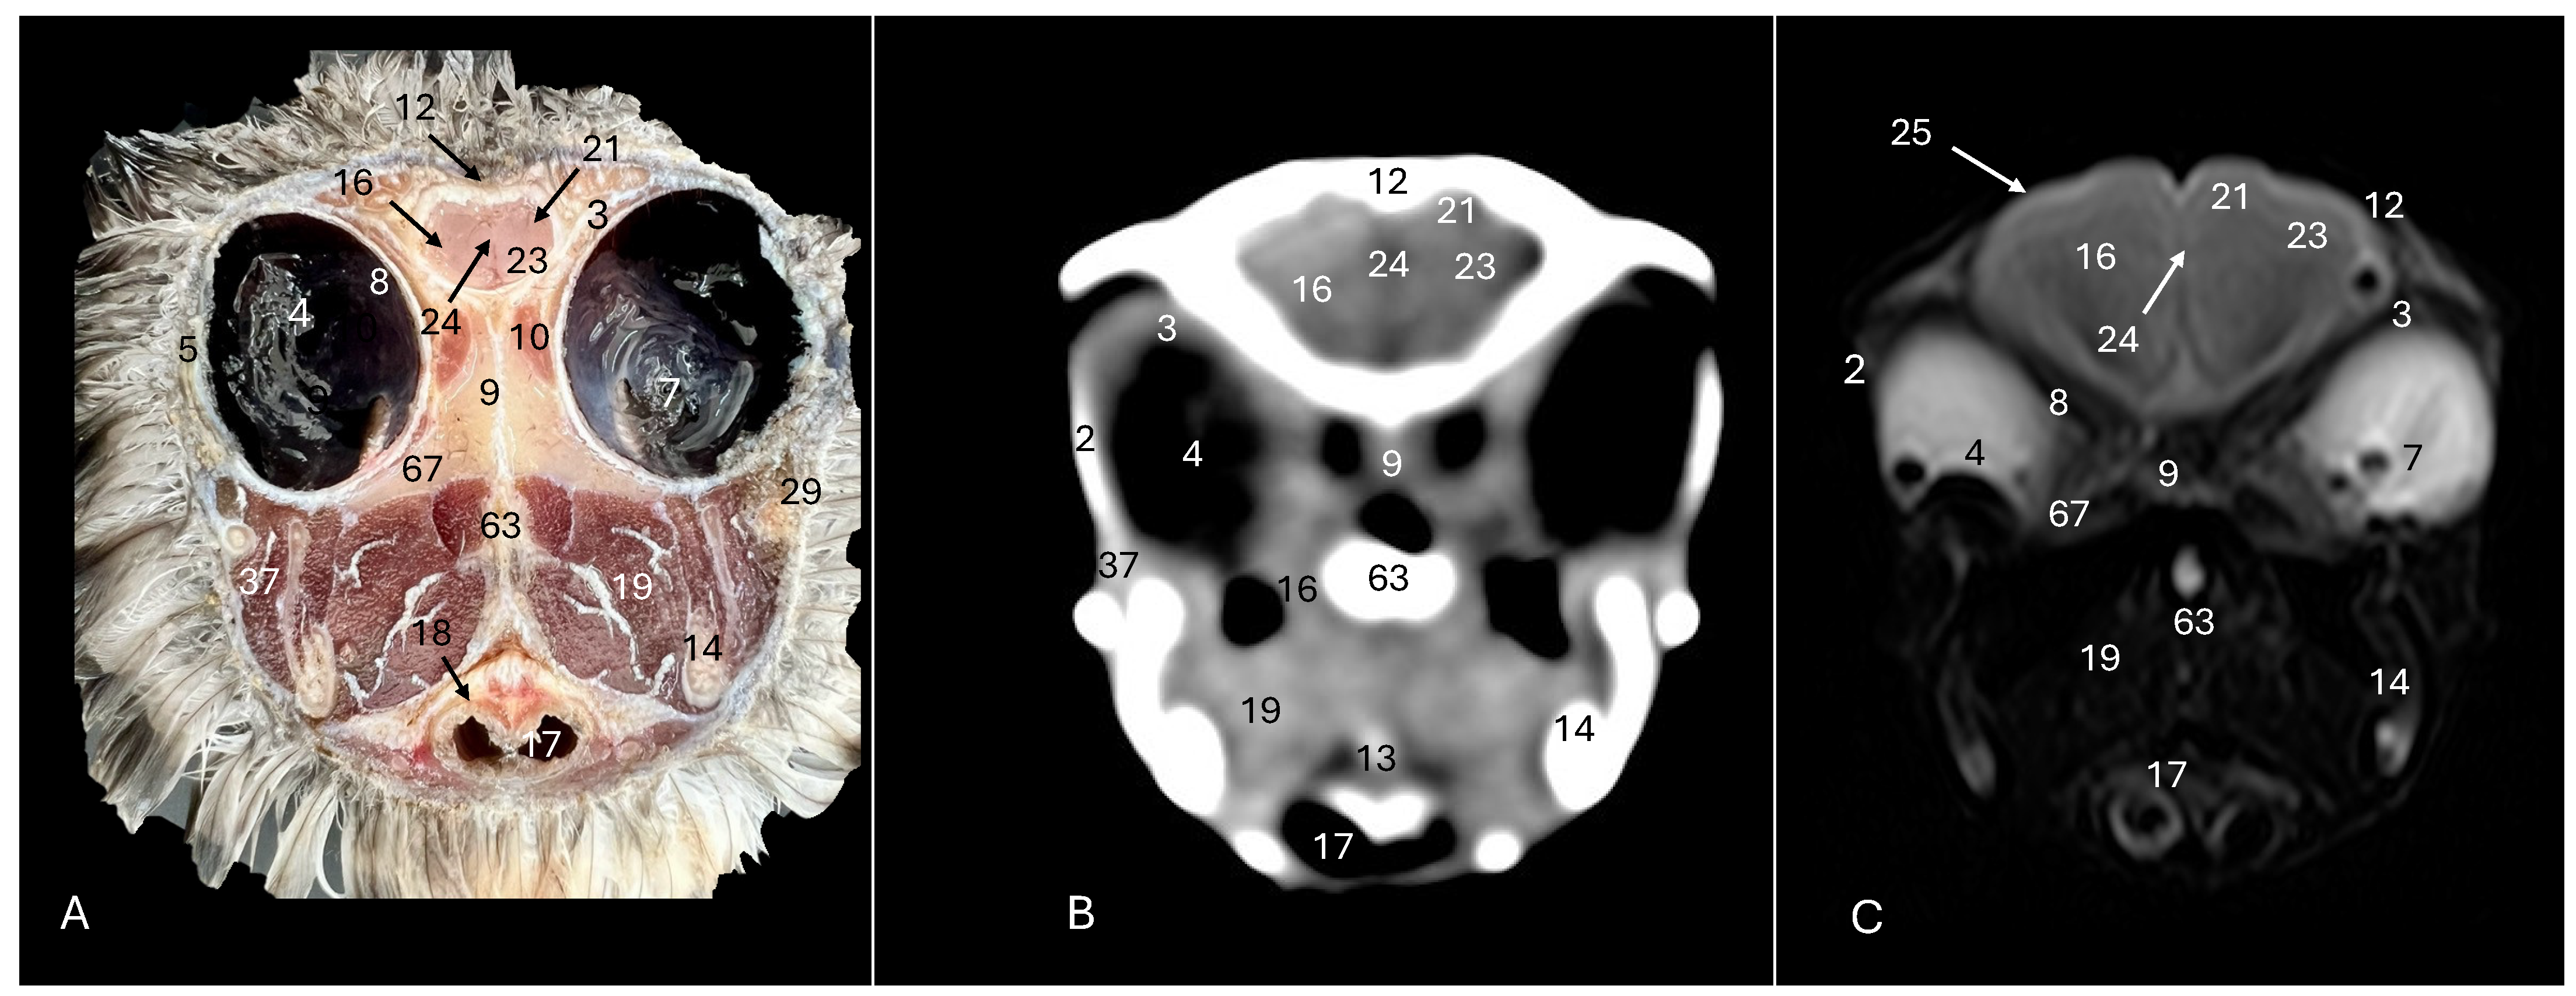

Cory’s Shearwater (Calonectris borealis): Exploring Normal Head Anatomy through Cross-Sectional Anatomy, Computed Tomography and Magnetic Resonance Imaging

3. Result

3.1. Anatomical Sections

3.2. Computed Tomography (CT)

3.3. Magnetic Resonance Imaging (MRI)